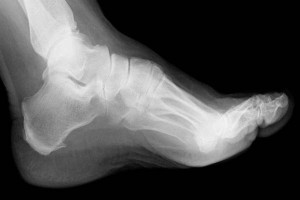

Kemik İltihabı Nedenleri ve Tedavisi

Genel olarak çocuklarda görülen bir kemik hastalığı olmaktadır. 12 yaşından sonra daha az görülmeyen başlayan kemik iltihabı, kısa sürede gelişen ve şiddetli belirtilerle kendini gösterir. Buna göre kemik iltihabı nedenleri ve tedavisi mümkündür. Öncelikle kemikte mantarlar ya da bakterilerden oluşan bir enfeksiyon hastalığı olmaktadır. Akut veya kronik olarak gözlenen yüksek ateş, terleme ve iltihabın yerleşmiş olduğu kemik bölgesinde yoğun olarak ağrı hissedilmektedir. Ayrıca kemik iltihabı nedenleri ve tedavisi çeşidine göre değişim göstermektedir. Kemik iltihabı bazen çok ani belirtiler verebilir. Kemiğin içinde bulunan irinin ani ve yüksek basınçla verdiği ağrı sonucu da ortaya çıkabilmektedir. Tabi ki kemik iltihapları nedenleri ve tedavisi mümkün olmaktadır.

Kemik iltihabı 3 hafta gibi bir sürede penisilin tedavisi ve antibiyotik ile azaltılmaktadır. Enfeksiyonun fonksiyonu ve boyutuna göre uygulanan tedaviler, genel anlamda başarılı sonuçlar getirirler. Sizde kemik iltihabı tedavisi için çözüm arıyorsanız, öncelikle doktorunuza başvurmalı, gerekli tetkikleri yaptırmalısınız. Gelişen ve genellikle tedavi edilen hastalığın belirtilerini dikkate almak gereklidir.